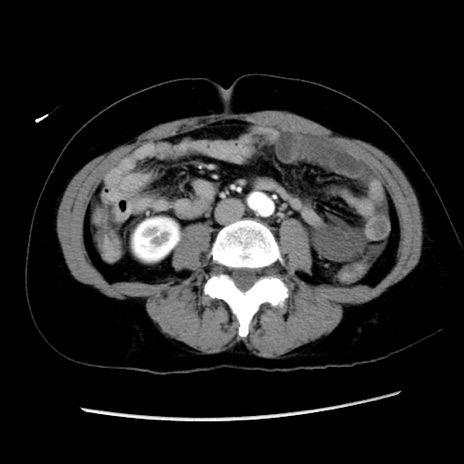

症例10(横断像)

【症例】 50歳代女性

【主訴】 腹痛

【現病歴】前日生レバーを食べた。今朝に排便あり。 昼前に突然発症の腹痛を生じ、当院救急外来を受診した。

【身体所見】 意識清明、腹部:平坦、軟、下腹部やや左を中心に圧痛・反跳痛あり、筋性防御あり

【データ】WBC 7800、CRP 0.07